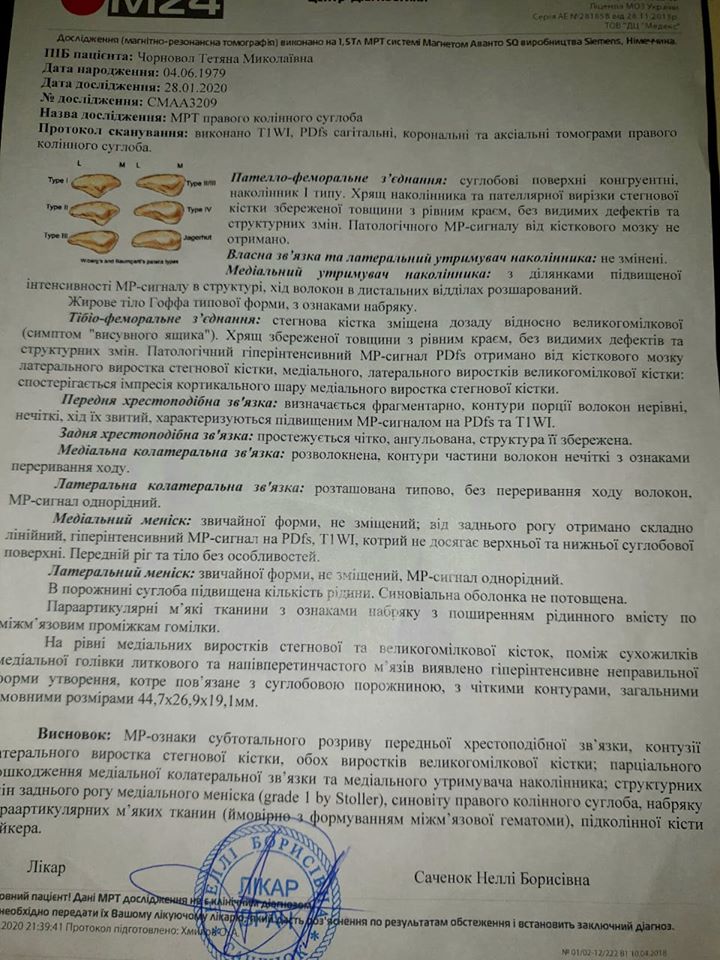

"Итак, после МРТ стало понятно, что у меня полностью оторвана передняя крестообразная связка. То есть, нога "гуляет" в колене. Это можно увидеть на фотографии МРТ, которую я прилагаю. На ней отчетливо видно заднюю крестообразную связку (она темная, сочетает бедренную и берцовую кость), а вот от передней видно только куски", - рассказала женщина.